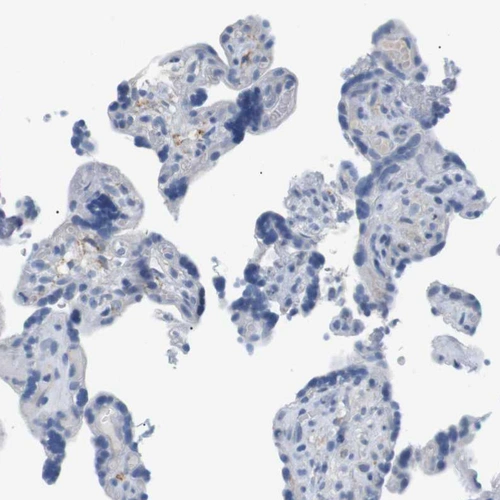

Immunohistochemical staining of human spleen shows weak membranous positivity in cells in red pulp.